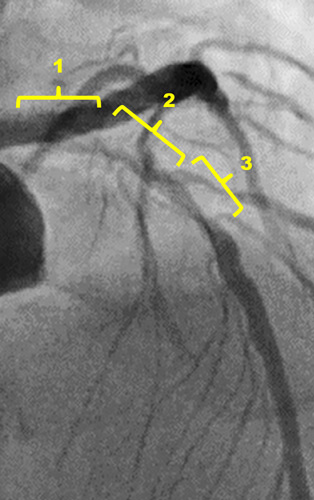

RCA shows diffuse atherosclerosis stenosis lesion, especially at the ostium.

The left coronary artery indicated 90% stenosis with severe calcification from the proximal to the middle part of LAD and diagonal branch

The image of IVUS showed 360 degree calcification at the middle part of LAD.

We decided to use rotablation for calcified plaque modification (extra-support wire, 1.5mm burr)